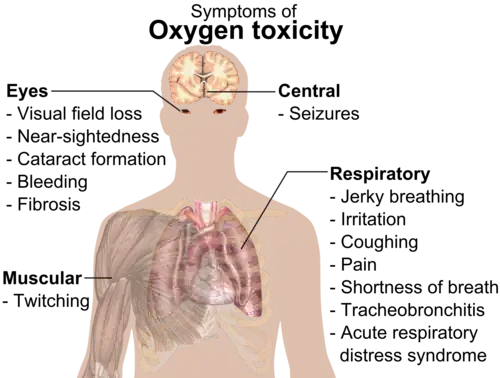

Toxicity

Oxygen gas (O

2) can be toxic at elevated partial pressures, leading to convulsions and other health problems.[134][h][154] Oxygen toxicity usually begins to occur at partial pressures more than 50 kilopascals (kPa), equal to about 50% oxygen composition at standard pressure or 2.5 times the normal sea-level O

2 partial pressure of about 21 kPa. This is not a problem except for patients on mechanical ventilators, since gas supplied through oxygen masks in medical applications is typically composed of only 30–50% O

2 by volume (about 30 kPa at standard pressure).[17]

At one time, premature babies were placed in incubators containing O

2-rich air, but this practice was discontinued after some babies were blinded by the oxygen content being too high.[17]

Breathing pure O

2 in space applications, such as in some modern space suits, or in early spacecraft such as Apollo, causes no damage due to the low total pressures used.[132][155] In the case of spacesuits, the O

2 partial pressure in the breathing gas is, in general, about 30 kPa (1.4 times normal), and the resulting O

2 partial pressure in the astronaut's arterial blood is only marginally more than normal sea-level O

2 partial pressure.[156]

Oxygen toxicity to the lungs and central nervous system can also occur in deep scuba diving and surface-supplied diving.[17][134] Prolonged breathing of an air mixture with an O

2 partial pressure more than 60 kPa can eventually lead to permanent pulmonary fibrosis.[157] Exposure to an O

2 partial pressure greater than 160 kPa (about 1.6 atm) may lead to convulsions (normally fatal for divers). Acute oxygen toxicity (causing seizures, its most feared effect for divers) can occur by breathing an air mixture with 21% O

2 at 66 m (217 ft) or more of depth; the same thing can occur by breathing 100% O

2 at only 6 m (20 ft).[157][158][159][160]